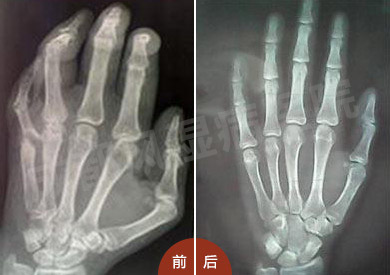

(图:患者治疗前后手部CT对比)

陈先生八年前在河南洛阳诊断患上类风湿性关节炎,因为对治疗认识不足,一直采用药物来止痛,控制病情。直到2013年患者病情恶化,双手多处关节出现变形情况。陈先生通过朋友介绍,来郑州痛风风湿病医院由王怀庆主任亲自诊治。经过3个疗程的诊治,陈先生关节异常症状消失,畸形关节得到矫正,活动能力 恢复,临床诊断各项指标达到健康标准可出院结束治疗。